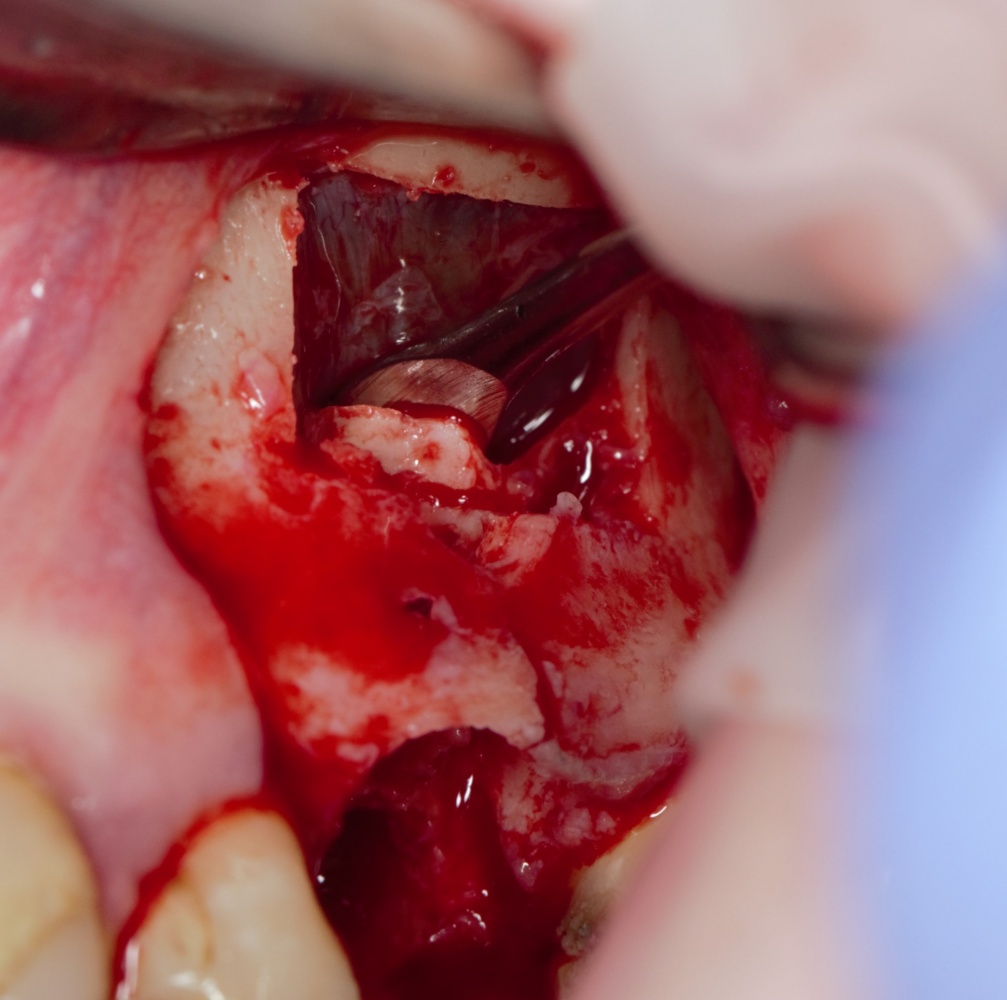

Как на фотографии выше — из-за целого ряда вмешательств и существовавшего ранее ороантрального соустья можно сказать, что от слизистой оболочки верхнечелюстной пазухи почти ничего не осталось. Можем ли мы как-то закончить эту работу? Легко:

Первая операция — мы не можем сразу поставить имплантат из-за почти полного отсутствия кости между полостью рта и дном верхнечелюстной пазухи: